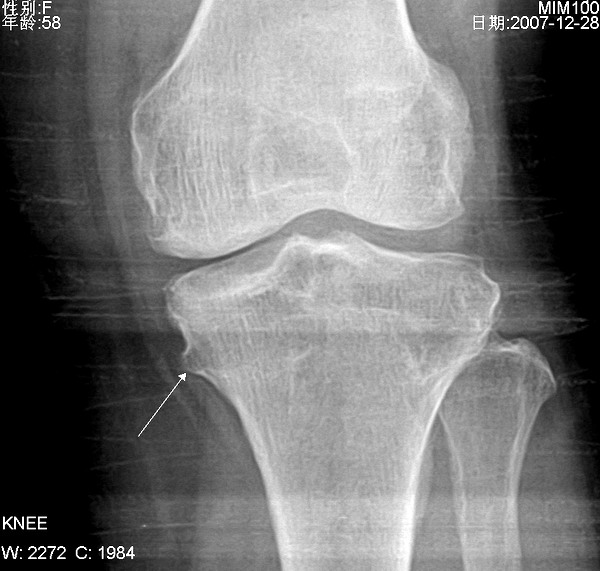

左侧膝关节疼痛

1、左膝关节退行性骨关节病伴关节积液。

2、胫骨干骺端骨软骨瘤。

左侧胫骨上干骺端内侧骨软骨瘤。

支持左侧胫骨近侧干骺端内侧骨软骨瘤。

1、左膝关节退行性骨关节病。

支持骨软骨瘤,关节积液看不出来。另有骨质增生。

左侧胫骨近侧干骺端内侧骨软骨瘤,左膝关节退行性骨关节病